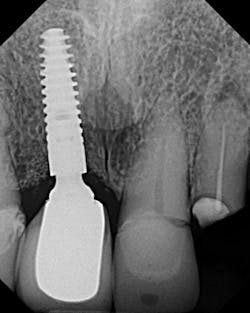

3. Tissue interferences, such as gingiva and/or bone between the abutment and fixture platform, should always be considered (especially in the posterior mandible) when misfit occurs. In addition, calculus, cement, and grafting material can also be lodge between mating surfaces of the abutment and fixture, and prevent seating (figure 2).